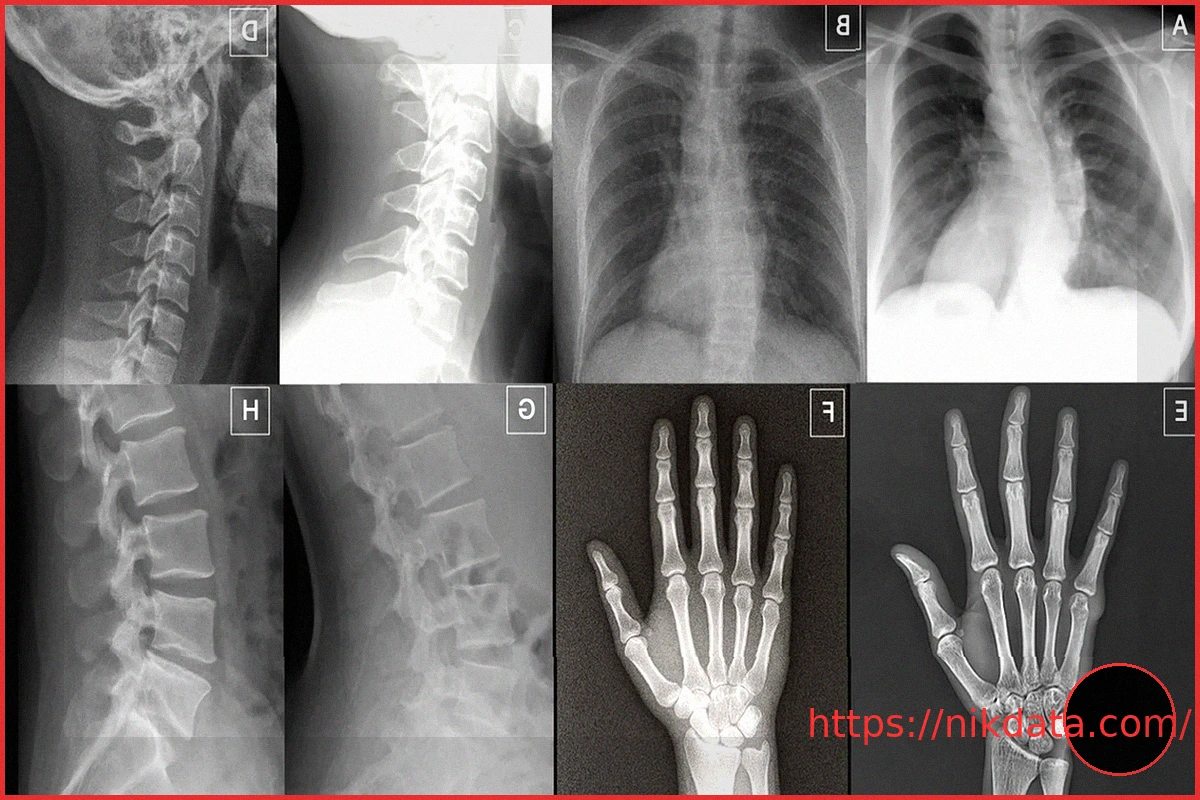

AI-generated deepfake X-rays have reached a level of realism capable of deceiving both human medical professionals and other AI systems. During tests, radiologists found it challenging to accurately identify these fabricated images, especially when they were unaware that fakes might be presented. This development introduces significant risks, such as fraudulent medical claims and the manipulation of diagnostic information. Experts stress the critical importance of developing stronger safeguards and advanced detection tools as this technology continues to evolve.